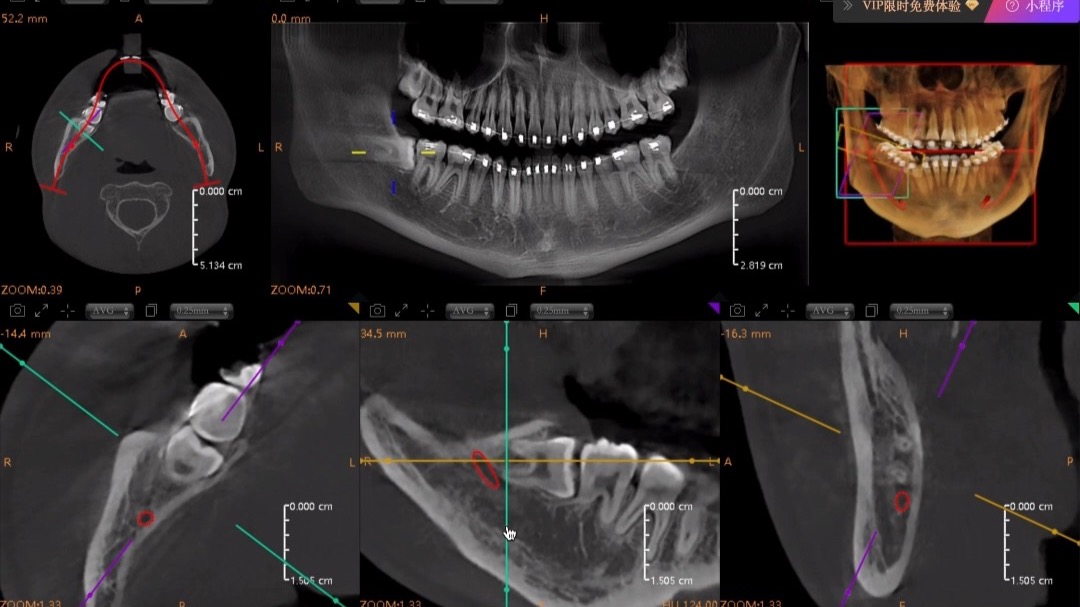

2025-07-3148水平阻生智齿拔除视频+解说

48水平阻生智齿,采用武大何克飞老师提出的改良T型分牙,